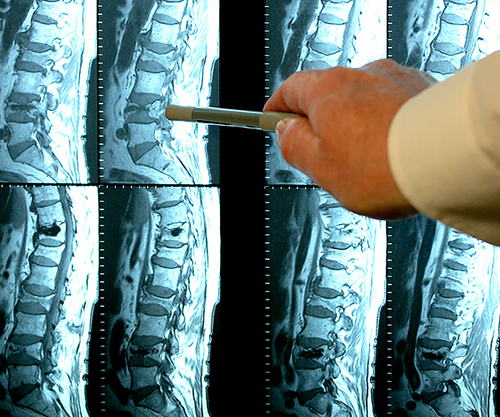

- กระดูกสันหลังเสื่อม